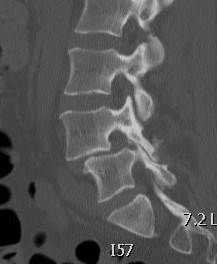

CT

Degeneration of facet